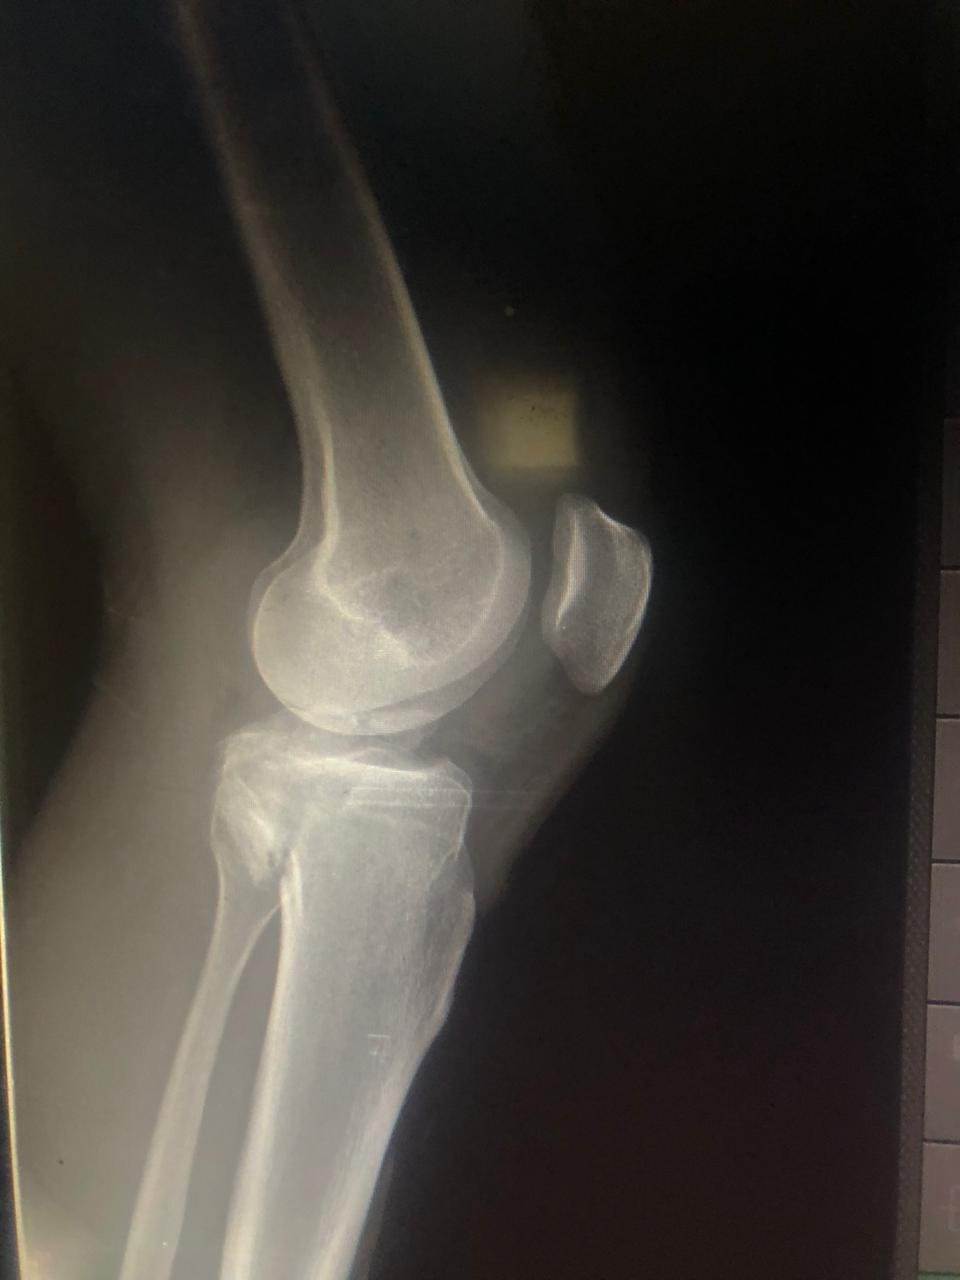

جراحة تثبيت داخلي لكسر متهتك بسطح مفصل الركبة بمستشفى بئر العبد

نجحت مستشفى بئر العبد التخصصى في إجراء جراحة لتثبيت داخلى لكسر متهتك بسطح مفصل الركبة.

وأعلن الدكتور تامر حمدى أحمد مدير عام المستشفى ( في بيان ) عن قيام الدكتور: أحمد ابراهيم سالم المدرس المساعد لجراحات المناظير واصابات الملاعب بالقصر العينى بجامعة القاهرة، الدكتور وسام عبد الفتاح أخصائى جراحة العظام بالمستشفى والدكتور محمود علم الدين أخصائى جراحة العظام بالمستشفى بجراحة تثبيت داخلى لكسر متهتك بسطح مفصل الركبة لمريض سقط من علو.

مشيرًا الى أن ذلك النوع من الكسور يكون قريبًا جدًا من الأعصاب والأوعية الدموية الرئيسية للساق والتي توجد خلف مفصل الركبة.. حيث تم الوصول الى الكسر وإعادة بناء سطح المفصل وتثبيته باستخدام شريحة ومسامير وأسلاك معدنية باستخدام جرح ٧ سنتيمترات خلف الركبة واستخدام مسامير جانبية مجوفة بدون فتح لتثبيت الجزء الخارجى من سطح المفصل، وتم الاطمئنان على الأوعية الدموية قبل إفاقة المريض، وبعد تمام الإفاقة.. تم الاطمئنان على الأعصاب والأوعية للمريض.

وأضاف أنه نظرًا لقرب هذا الكسر من سطح المفصل تم عمل أشعة مقطعية بعد الجراحة للتأكد من جودة بناء المفصل وعدم وجود أى بروز للمسامير داخل المفصل، وجارٍ تحضير المريض لعمل رنين مغناطيسى لتحديد الأربطة الداخلية والخارجية للركبة التي ستحتاج لإعادة بناء بالمنظار.